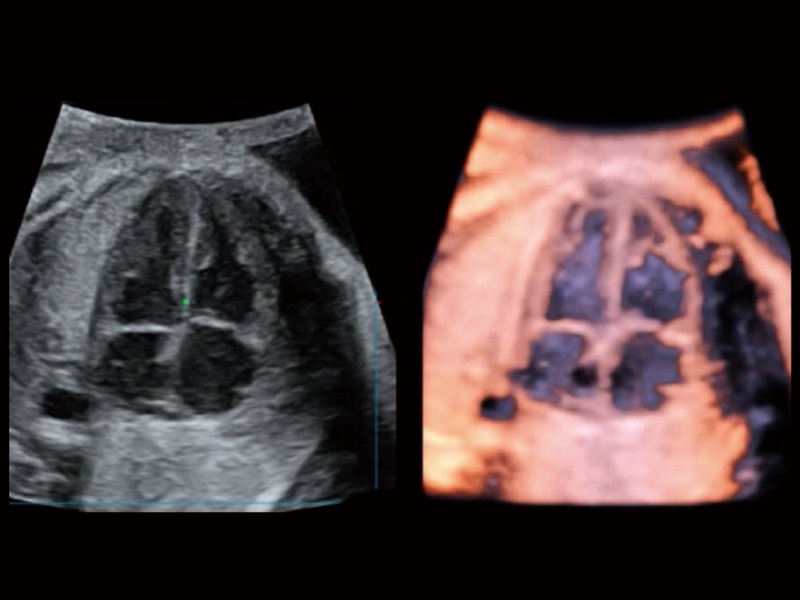

STIC

Zamansal ve mekânsal boyutlar boyunca frame ratelerin ortalamasını alarak, STIC farklı düzlemlerde görüntüler oluşturur; böylece hızla hareket eden fetal kalp yapılarını farklı açılardan kapsamlı bir şekilde inceleme ve değerlendirme olanağı sağlar.